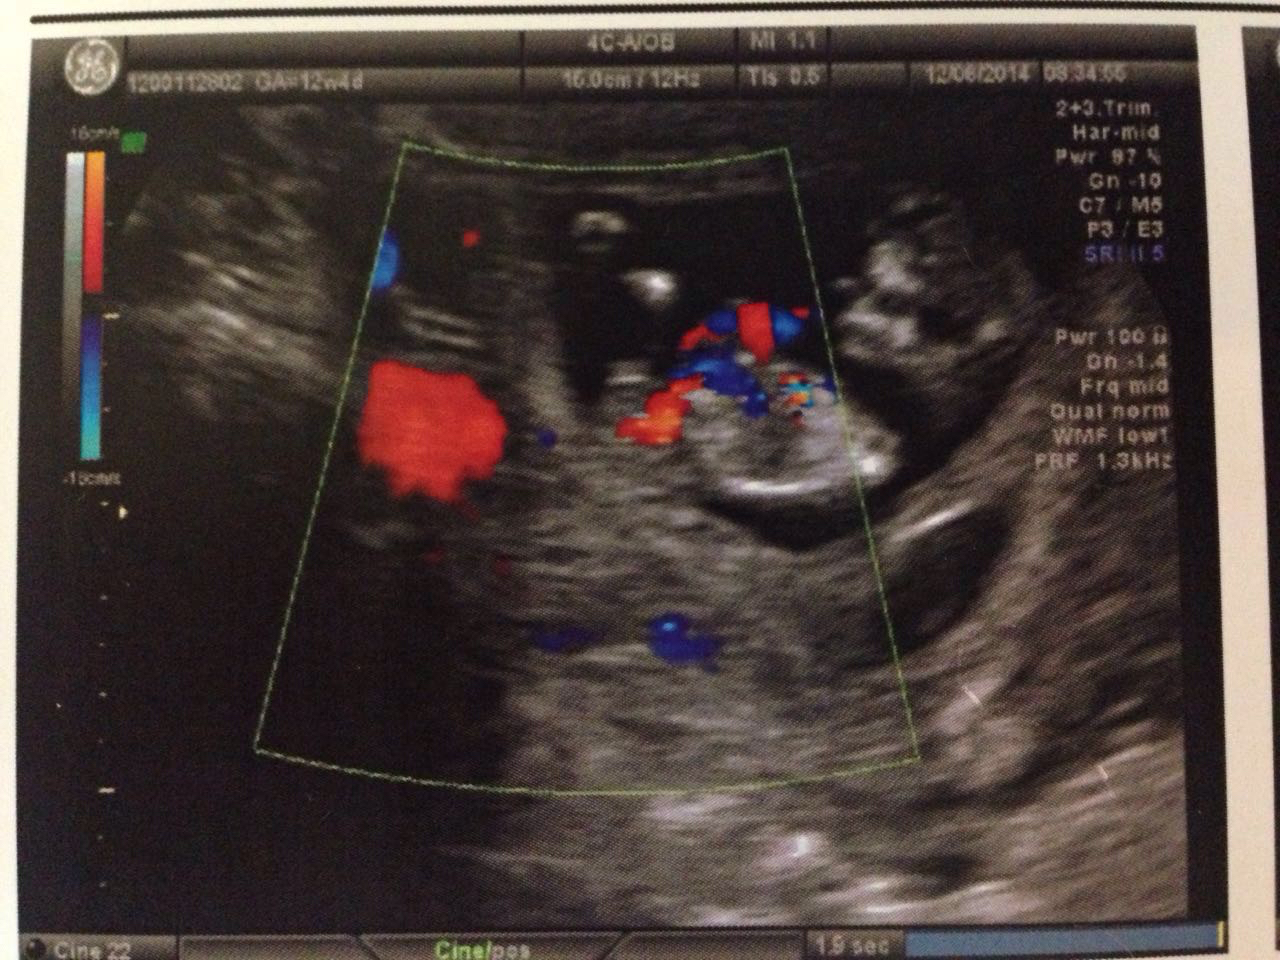

IMG_6235 Share this: Share on Facebook (Opens in new window) Facebook Share on X (Opens in new window) X More Email a link to a friend (Opens in new window) Email Share on Pinterest (Opens in new window) Pinterest Print (Opens in new window) Print Like Loading...